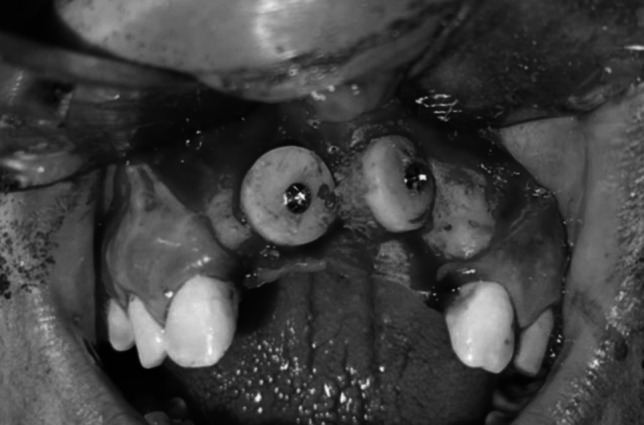

有许多因素可以影响下颌缺陷的矫正和特定移植材料的成功,包括上颌和下颌骨的组织学和密度以及移植材料本身。本研究比较了使用混合可注射富血小板纤维蛋白(i-PRF)或异种移植物的下颌联合嵌骨移植增强前上颌水平牙槽嵴的临床结果。将12例成人上颌牙槽嵴水平缺损患者随机分为两组,每组6例。I组采用下颌联合嵌骨移植物混合I - prf, II组采用下颌联合嵌骨移植物混合异种移植物(InterOss有机松质颗粒)。术前和随访6个月时采用CBCT扫描测量牙槽嵴宽度和骨密度。两组牙槽嵴宽度和骨密度均有改善。6个月后测量骨宽度和骨密度的增加,II组显著大于I组(p = 0.040)。水平牙槽嵴增强术采用嵌板下巴移植物结合异种移植物是成功的,并提供了足够的骨数量和质量。

There are numerous factors that can impact both the correction of jaw deficiencies and the success of a particular grafting material, including the histology and density of both the maxillary and mandibular bones and the grafting material itself. This study compares the clinical outcomes of grafted augmentations of the horizontal alveolar ridge of the anterior maxilla using mandibular symphysis onlay bone that was admixed with either injectable platelet-rich fibrin (i-PRF) or xenografts. Twelve adult patients with horizontal maxillary alveolar ridge deficiency were randomly divided into two groups of six patients each. Group I received mandibular symphysis onlay bone grafts mixed with i-PRF, while Group II received mandibular symphysis onlay bone grafts admixed with xenografts (InterOss anorganic cancellous granules). CBCT scans were used to measure alveolar ridge width and bone density both preoperatively and at 6-month follow-up. Both groups showed improvements in alveolar ridge width and bone density. The increase in measured bone width and density after 6 months in Group II was significantly greater than that in Group I (p = 0.040). Horizontal alveolar ridge augmentation using an onlay chin graft in combination with xenografts was successful and offered adequate bone quantity and quality.